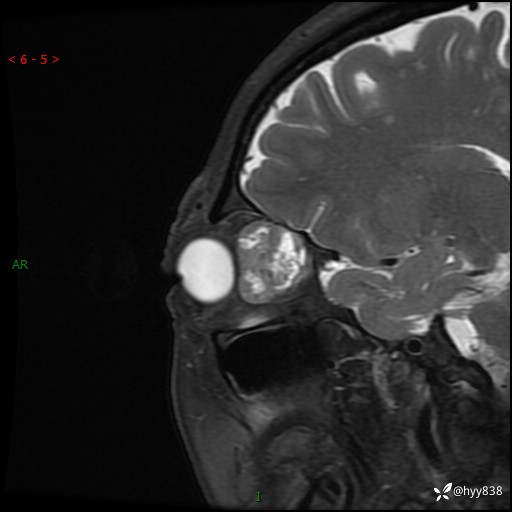

老年女性,右眼球突出1月。说说鉴别诊断,看谁第一个秒---(有结果)

主诉:发现右眼球突出1月余

简要病史:患者于1月前无明显诱因发现右眼球突出,偶感磨痛、眼胀,无视力下降,无头痛,恶心呕吐等不适。10天前就诊于当地县人民医院就诊,完善头颅ct检查,诊断为右侧眼眶肿物,建议患者上级医院进一步治疗,患者因个人原因拒绝。拟行手术,来我院就诊,门诊行相关检查后以“右眼眼眶肿物”收入院。 患病以来,患者精神饮食睡眠尚可,大小便如常、体重无明显改变。

辅助检查:MRI

临床诊断:眼眶肿物

眼眶MRI平扫+增强